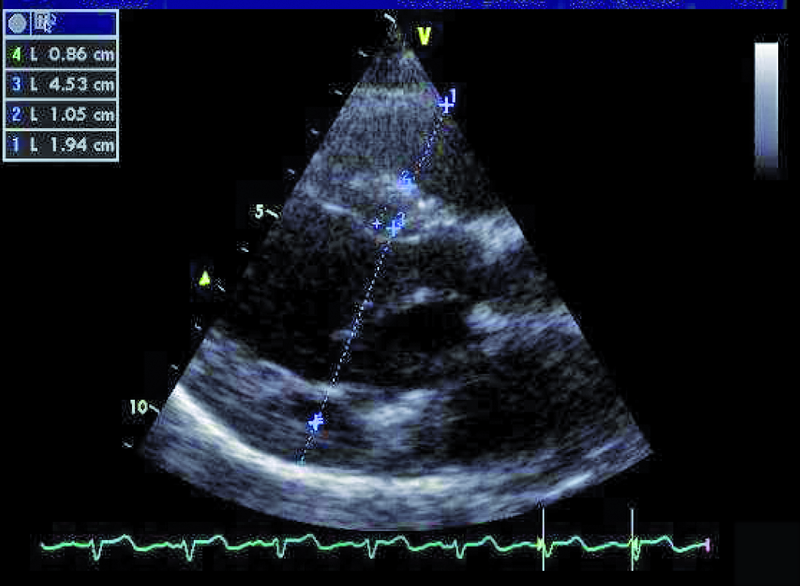

Przedstawiona chora, prawie dorosła kobieta, znajduje się w tej drugiej grupie. Jamy serca są u niej niepowiększone, a mięsień ma prawidłową grubość (ryc. 1). Rozpoznanie membrany w jamie lewego przedsionka z prawidłowym obrazem zastawki mitralnej nie nastręcza trudności. Membranę można dostrzec w wielu projekcjach (ryc. 2-4). Badanie przezprzełykowe pozwala na bardziej precyzyjne określenie średnicy otworu, która zazwyczaj waha się od kilku milimetrów do centymetra. W omawianym przypadku otwór jest duży i na podstawie samej jego wielkości można przypuszczać, że nie powoduje obstrukcji przepływu (membrana w projekcji na rycinie 4 znajduje się powyżej zastawki). Tryb doplera ciągłego (ryc. 5) także nie potwierdza zaburzeń przepływu i trudno się spodziewać, by w takiej sytuacji mogło dojść do podwyższenia ciśnienia w żyłach płucnych, włośniczkach i pniu płucnym. Średnica pnia płucnego (21 mm, ryc. 6) jest dowodem na panujące w nim niskie ciśnienie (nie zarejestrowano w badaniu fali zwrotnej trójdzielnej). Serce trójprzedsionkowe z niskim gradientem śródprzedsionkowym przy braku dodatkowych nieprawidłowości (np. przecieku międzyprzedsionkowego lewo-prawego bądź prawo-lewego – zależnie, z jaką jamą ubytek się komunikuje) nie wymaga leczenia operacyjnego. Pacjentka wymaga dalszej kontroli, ponieważ po wielu latach choroby mogą pojawić się napadowe lub utrwalone nadkomorowe zaburzenia rytmu serca, będące wyrazem zmiany geometrii przedsionka.